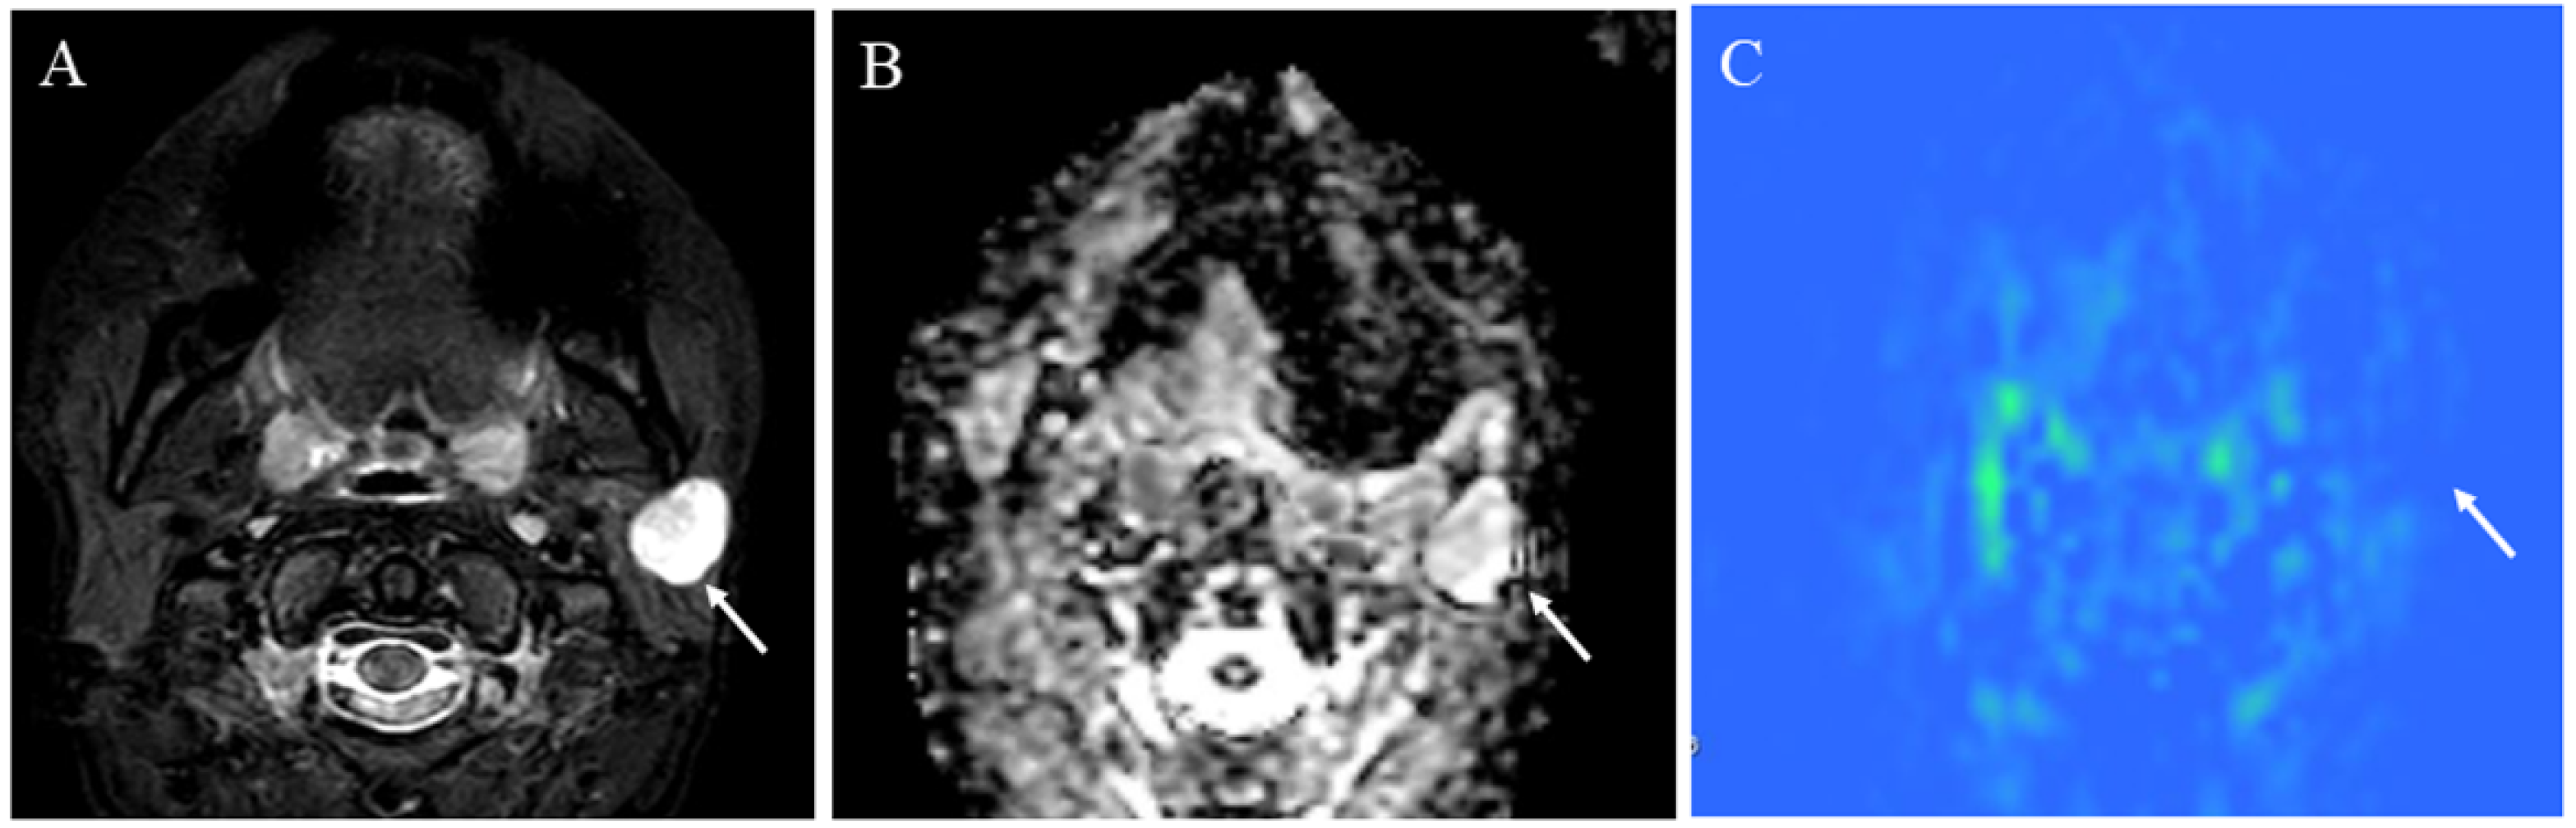

Figure 9. A 72-year-old male with acinic cell carcinoma of the right parotid gland: (A) STIR shows a mass with high signal intensity (arrow); (B) ADC map shows mild restricted diffusion (arrow) (ADC 10th percentile, 0.93 × 10−3 mm2/s and ADC mean of 1.03 × 10−3 mm2/s); (C) pCASL image shows high TBF (arrow) (TBF 50th percentile, 34.26 mL/100 g/min).